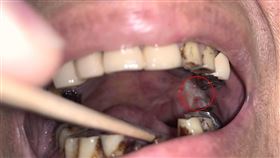

58歲男嘴破2個月好不了!醫一看:罹癌了

南投58歲王先生曾有20年菸齡,在兩個月前發現自己一...

致癌三寶不離身 舌癌男治癒又罹這癌

台中50歲張先生十多年來抽菸、喝酒、嚼檳榔樣樣來,去...